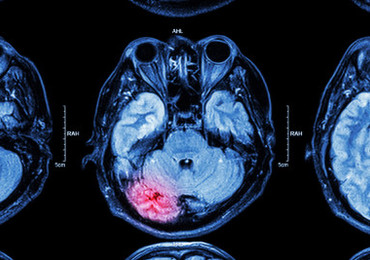

La recherche en neurologie est de plus en plus confrontée à un paradoxe: alors que les outils d’imagerie cérébrale et de neurophysiologie ont connu des avancées technologiques majeures, les bases de données disponibles pour l’analyse à grande échelle restent souvent limitées en taille, en diversité ou en représentativité clinique. Dans ce contexte, la Brain Imaging and Neurophysiology Database (BIND), décrite dans un préprint publié sur medRxiv en octobre 2025, semble constituer une avancée méthodologique majeure pour la recherche translationnelle et clinique en neurosciences.

En routine clinique depuis des dizaines d’années, l’échelle de Glasgow reste l’outil de référence pour la stratification initiale des traumatismes crâniens (TC). Elle est simple d’utilisation, mais elle souffre d’importantes limitations, comme une faible sensibilité pour les formes légères, un manque de prise en compte des comorbidités et une valeur pronostique perfectible.